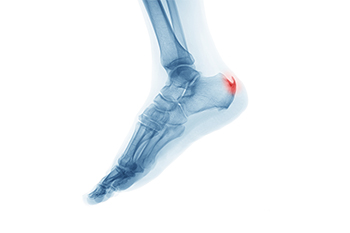

Do I Have Heel Spurs?

Many people have heel spurs and don’t even know it. Heel spurs are actually calcium deposits in the heel of the foot, and can grow up to half-an-inch long. Most often they cause a dull ache or tenderness, and sometimes a sharp pain in the morning when you first stand up. Extreme heel pain is more often caused by plantar fasciitis, but the two conditions are often linked. The most common causes of heel spurs are running on hard surfaces, obesity, and wearing non-supportive footwear, such as flip-flops. If you frequently experience severe heel pain, please see a podiatrist for diagnosis and treatment.

Heels Spurs

Heel spurs are formed by calcium deposits on the back of the foot where the heel is. This can also be caused by small fragments of bone breaking off one section of the foot, attaching onto the back of the foot. Heel spurs can also be bone growth on the back of the foot and may grow in the direction of the arch of the foot.

Older individuals usually suffer from heel spurs and pain sometimes intensifies with age. One of the main condition's spurs are related to is plantar fasciitis.

Pain

The pain associated with spurs is often because of weight placed on the feet. When someone is walking, their entire weight is concentrated on the feet. Bone spurs then have the tendency to affect other bones and tissues around the foot. As the pain continues, the feet will become tender and sensitive over time.